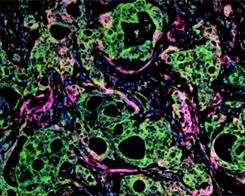

组织交叉反应( Tissue Cross-Reactivity,TCR) 试验是指在体外检测单抗或相关抗体样生物制品与组织上的抗原决定部位结合的试验,常用检测方法为免疫组织化学技术(Immunohistochemistry, IHC)。免疫组织化学,又称免疫细胞化学试验,其原理为用标记的抗体或抗原对组织相应抗原或抗体进行定性、定位或定量检测,经化学呈色反应后用显微镜或电子显微镜进行观察。随着新技术的发展,组织芯片、Western Blot、流式细胞术(对培养细胞或外周血样本)等试验技术也开始应用于TCR试验。

图1.免疫组化 IHC 细胞浆表达

图2.组织芯片免疫组化(IHC)染色